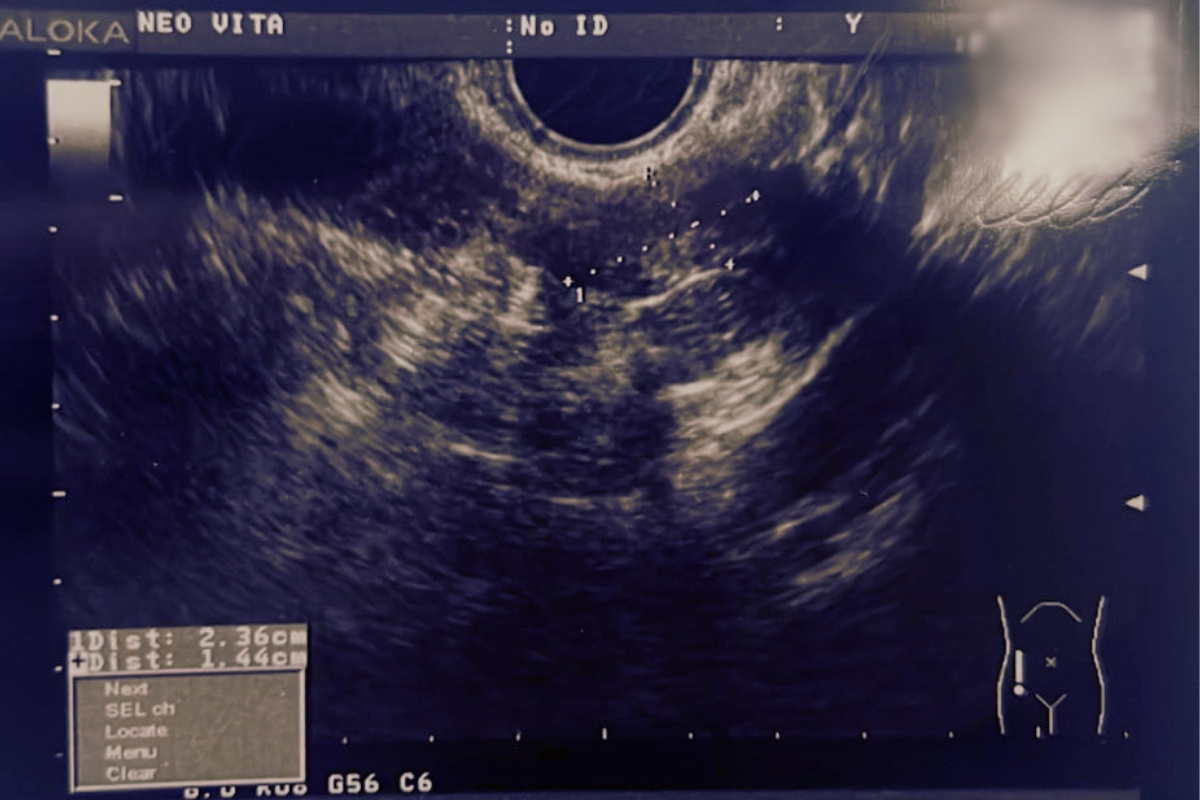

Показания врачей в другой клинике: предложено хирургическое лечение в объеме надвлагалищной ампутации матки без придатков (выявлен крупный интерстициально-субмукозный миоматозный узел 6х4.7х 5.2 см.)

Далее пациентка прошла курс лечения телесной терапии и лекарственными препаратами у нашего остеопата и гинеколога. Пациентке трижды производилось ультразвуковое исследование малого таза: через три месяца после прохождения программы и через 6 месяцев

Результаты лечения Вы можете видеть на фото.

В начале 2024 года начались задержки менструального цикла, до 2-х недель, обильные и болезненные выделения. На УЗИ размер нескольких миоматозных узлов уже 48х 37 мм, 28 х 35 мм, 43 х36 мм. Так как наблюдался рост новообразований были показания к операции и в другой клинике меня направили на операцию. Я не хотела делать операцию и принимать гормональную терапию и обратилась в Центр лечения миомы без операции при клинике Нео Вита по рекомендации.

На сегодняшний день нормализовался цикл, ушла боль, улучшилось настроение и общее состояние. Значительно изменились процессы в личной жизни- это тоже хочу отметить. Размеры узлов 23 х14,12 х15 мм. Это большой прогресс, ведь я понимаю, когда убрать у болезни причину – она не вернется и терапия медикаментозная на нужных этапах лечения действительно быстро помогает.